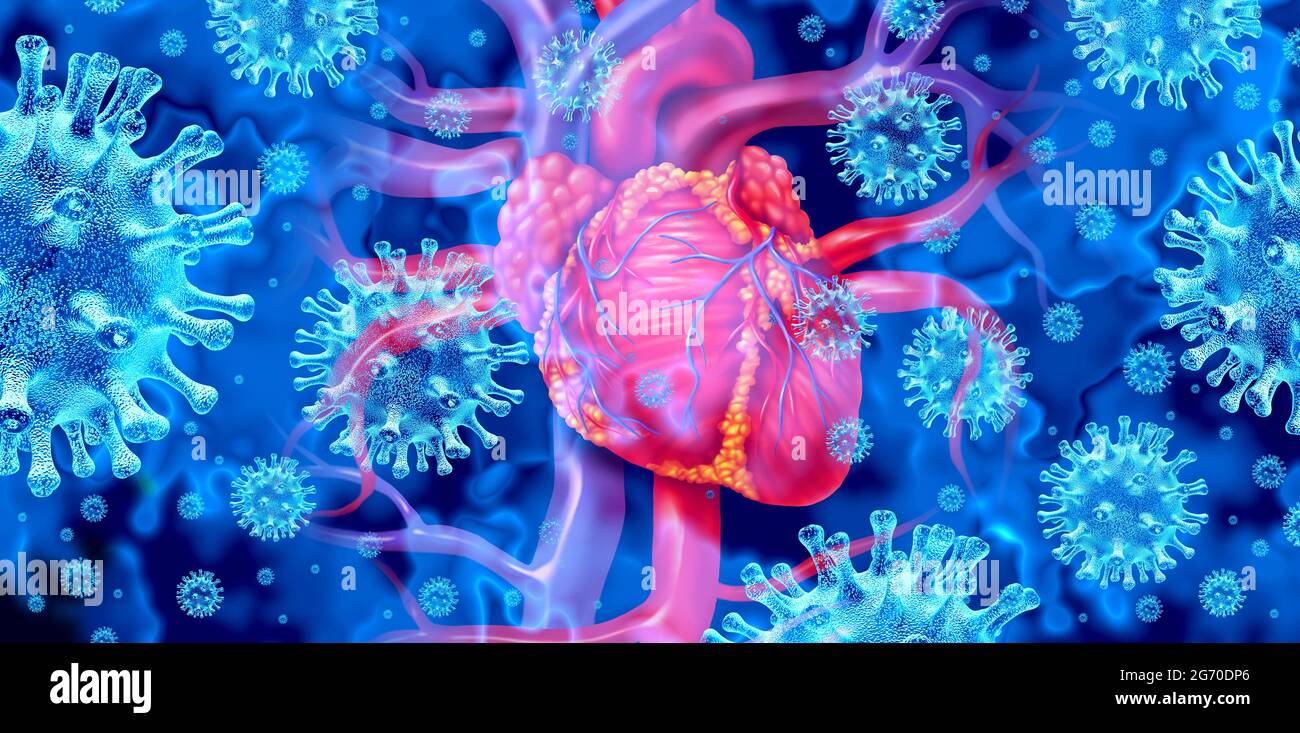

Myocarditis disease or virus infection of the human heart resulting in inflammation of the cardiac circulatory organ. Stock Photohttps://www.alamy.com/image-license-details/?v=1https://www.alamy.com/myocarditis-disease-or-virus-infection-of-the-human-heart-resulting-in-inflammation-of-the-cardiac-circulatory-organ-image455237864.html

Myocarditis disease or virus infection of the human heart resulting in inflammation of the cardiac circulatory organ. Stock Photohttps://www.alamy.com/image-license-details/?v=1https://www.alamy.com/myocarditis-disease-or-virus-infection-of-the-human-heart-resulting-in-inflammation-of-the-cardiac-circulatory-organ-image455237864.htmlRF2HCHTF4–Myocarditis disease or virus infection of the human heart resulting in inflammation of the cardiac circulatory organ.

Viral myocarditis or virus infection of the human heart resulting in inflammation of the cardiac circulatory organ with 3D illustration elements. Stock Photohttps://www.alamy.com/image-license-details/?v=1https://www.alamy.com/viral-myocarditis-or-virus-infection-of-the-human-heart-resulting-in-inflammation-of-the-cardiac-circulatory-organ-with-3d-illustration-elements-image434572606.html

Viral myocarditis or virus infection of the human heart resulting in inflammation of the cardiac circulatory organ with 3D illustration elements. Stock Photohttps://www.alamy.com/image-license-details/?v=1https://www.alamy.com/viral-myocarditis-or-virus-infection-of-the-human-heart-resulting-in-inflammation-of-the-cardiac-circulatory-organ-with-3d-illustration-elements-image434572606.htmlRF2G70DP6–Viral myocarditis or virus infection of the human heart resulting in inflammation of the cardiac circulatory organ with 3D illustration elements.